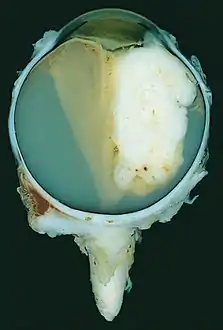

![]() | |

| A pathology specimen of a retinoblastoma tumor from an enucleated eye of a 3-year-old female | |

Morphology

Gross and microscopic appearances of retinoblastoma are identical in both hereditary and sporadic types. Macroscopically, viable tumor cells are found near blood vessels, while zones of necrosis are found in relatively avascular areas. Microscopically, both undifferentiated and differentiated elements may be present. Undifferentiated elements appear as collections of small, round cells with hyperchromatic nuclei; differentiated elements include Flexner-Wintersteiner rosettes, Homer Wright rosettes,[29] and fleurettes from photoreceptor differentiation.[30]